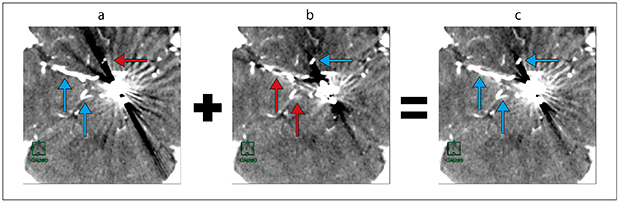

FBP・O-MAR・fusion画像

FBP・O-MAR・fusion画像を紹介する。頭部3D-CTAのFBP元画像は,金属アーチファクトのため前大脳動脈の描出が不良である(図1 a)。O-MAR元画像では金属アーチファクトは低減され,前大脳動脈の描出は良好であるが,新たに発生したアーチファクトにより右中大脳動脈と右上小脳動脈が描出不良となっている(図1 b)。fusion元画像は,金属アーチファクトも低減しており,FBP・O-MAR両画像の血管最大CT値で再構成されるため血管描出が良好である(図1 c)。

図1 頭部3D-CTA元画像(→:描出良好,→:描出不良)

a:FBP。金属アーチファクトにより前大脳動脈の描出不良である(←)。

b:O-MAR。金属アーチファクトは低減され前大脳動脈の描出良好である(←)。しかし,新たなアーチファクトが発生し右中大脳動脈・右上小脳動脈が描出不良である(↑)。

c:fusion。金属アーチファクトも低減され,すべての血管が描出良好である(←)。